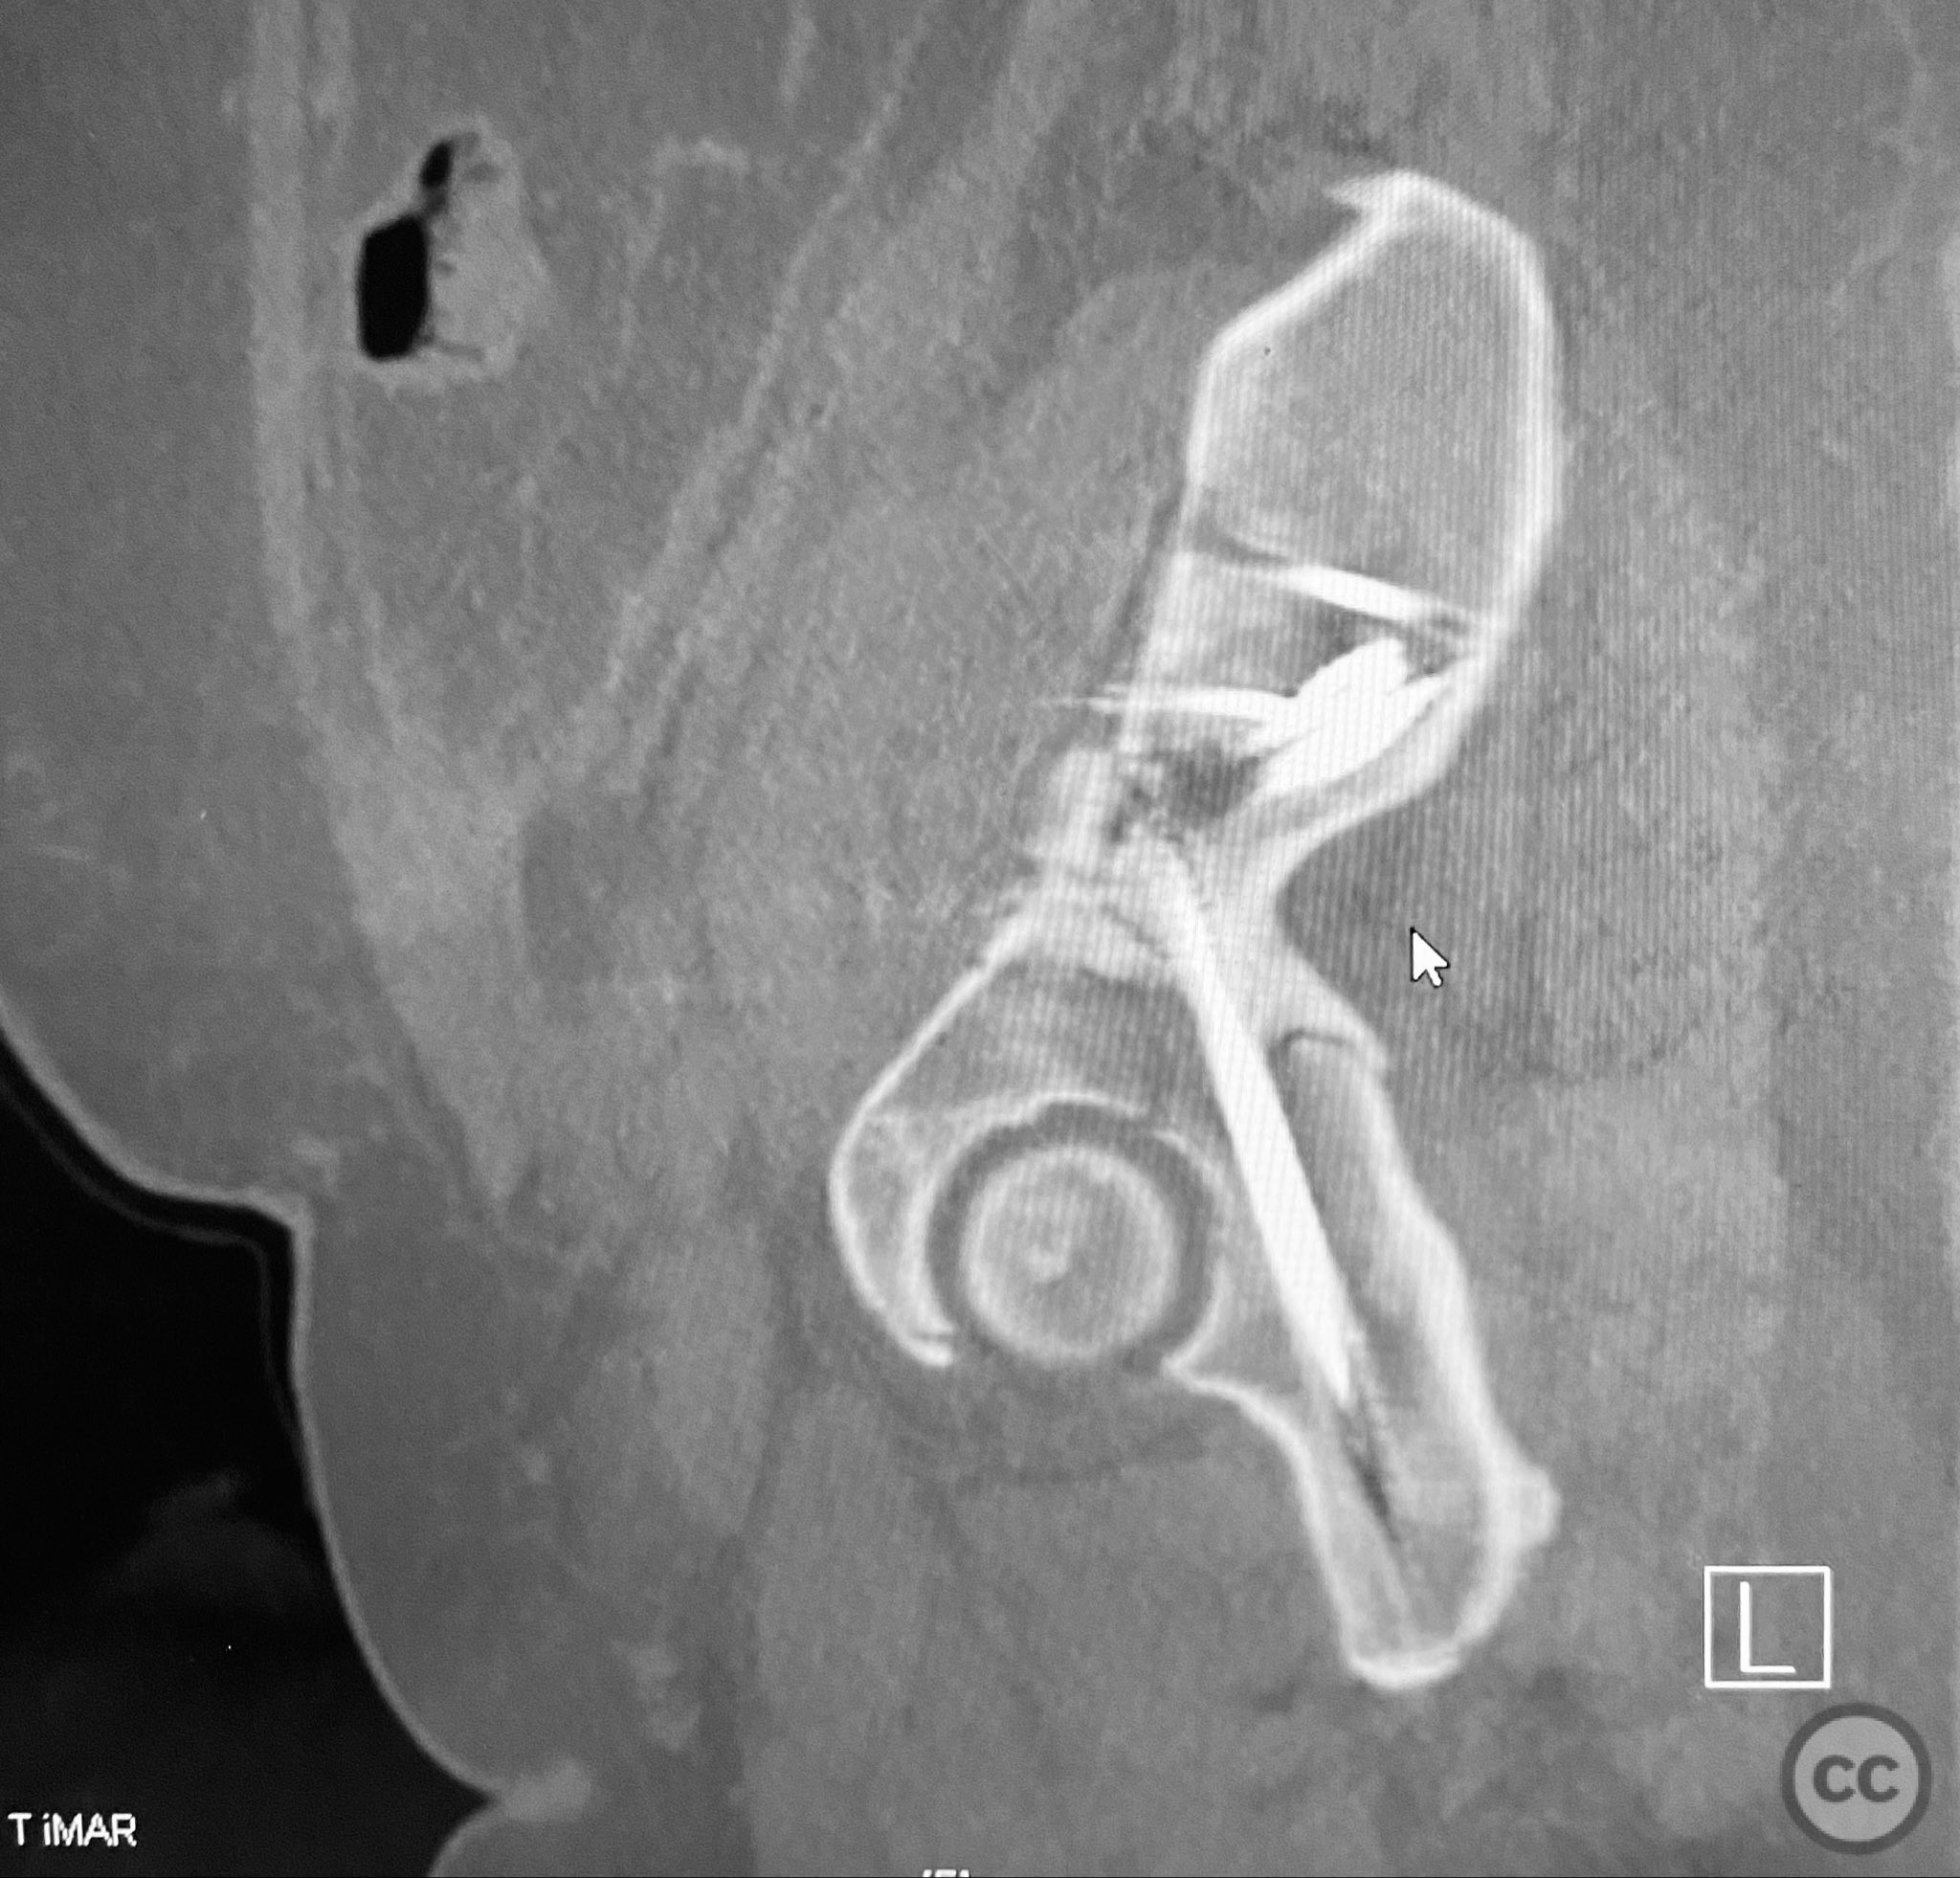

Clinical and radiological findings:  A patient presented with a displaced associated both column acetabular fracture, characterized radiographically by the presence of the "spur sign" on the anteroposterior (AP) pelvis film, indicating the caudal aspect of the intact ilium exposed by medial displacement of the articular fragments. The spur was more clearly visualized on the obturator oblique rendered image. Axial computed tomography (CT) images demonstrated the intact ilium, medially displaced anterior column (AC) and posterior column (PC) fragments, and provided detailed visualization of surrounding soft tissues, including vascular structures enhanced by contrast. Multiplanar CT reconstructions (axial, sagittal, coronal) and 3D renderings were utilized for comprehensive fracture and soft tissue assessment. The patient’s overall clinical condition was a significant factor in surgical planning.

Planning remarks:  The preoperative plan involved open reduction and internal fixation (ORIF) of the anterior column via the ilioinguinal approach, utilizing two separate windows for exposure and reduction. Given the patient’s clinical status, a staged approach was selected: initial AC reduction and fixation, with planned subsequent percutaneous reduction and fixation of the PC. Implant positioning during the first operation was planned to avoid obstructing subsequent percutaneous PC fixation.

Anatomical surgical approach:  A classical ilioinguinal approach was performed, with two windows developed: the lateral window between the musculus sartorius and musculus tensor fasciae latae, and the middle window between the musculus iliopsoas and external iliac vessels. Subcutaneous dissection was performed to create two opposing slabs of adipose tissue ("walls of fat"), minimizing random subcutaneous incisions. The anterior column fragment was exposed, reduced anatomically, and fixed under direct visualization. At a subsequent stage, percutaneous reduction and fixation of the posterior column were performed under fluoroscopic guidance, with careful trajectory planning to avoid interference from previously placed AC implants.